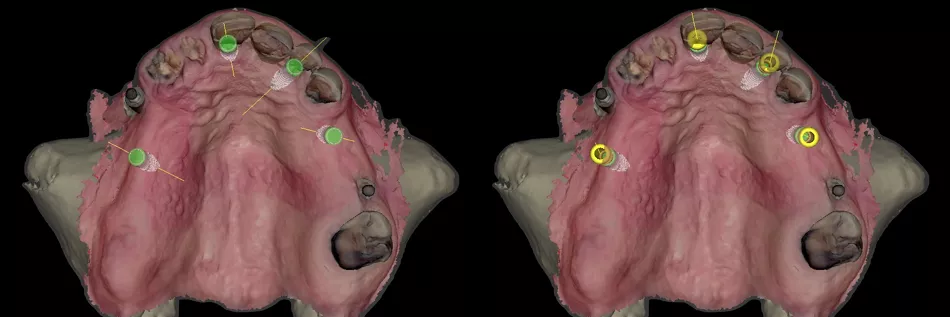

The seating surfaces of the Novaloc® abutments were verified, ensuring they were free of residue and dry. The Novaloc® Scanbodies were then placed on each Novaloc® abutment and pressed down firmly to ensure proper seating (Figs. 57,58).

Printed models were fabricated from intraoral scans, and the final upper and lower removable prostheses with a resin and metal framework were prepared in advance, prior to the extraction of the remaining teeth and removal of failed old implants (Figs. 59,60).

The upper and lower prostheses were evaluated, with occlusal and basal views of the lower prosthesis taken prior to the placement of the Novaloc® matrices (Figs. 61,62).